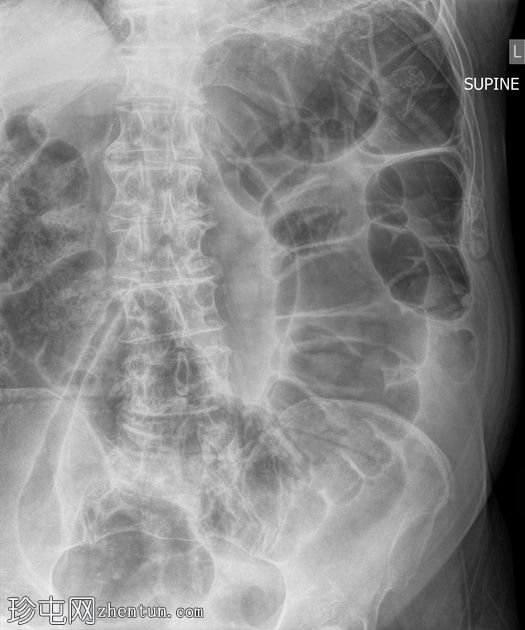

正位片

大肠袢扩张,呈“咖啡豆征”,直肠内未见气体,提示乙状结肠扭转。